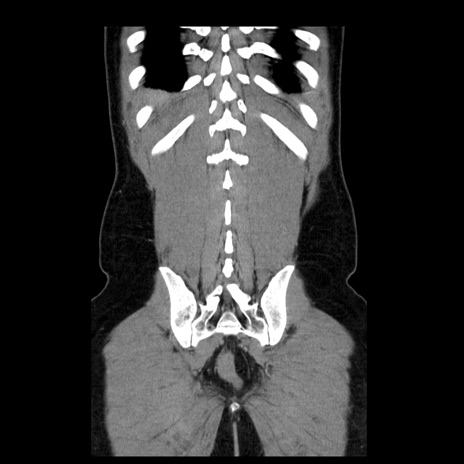

症例4(冠状断像)

【症例】30歳代男性

【主訴】腹痛、嘔吐

【現病歴】昨晩から突然の腹痛あり、その後嘔吐、軟便も出現。腹痛が改善しないため救急搬送となる。2日前にしめ鯖の食事歴あり。

【身体所見】意識清明、苦悶様、BP 135/90mmHg、BT 35.7℃、腹部:平坦、やや硬、心窩部〜臍部に自発痛、圧痛あり、筋性防御+、反跳痛-

【データ】WBC 8100、CRP 0.57